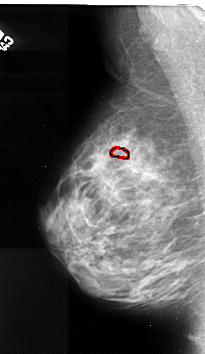

A_1105_1.RIGHT_CC

RIGHT_CC LINES 4381 PIXELS_PER_LINE 2671 BITS_PER_PIXEL 16 RESOLUTION 42 NON_OVERLAY

FILE: A_1105_1.LEFT_MLO.OVERLAY

TOTAL_ABNORMALITIES 1

ABNORMALITY 1

LESION_TYPE CALCIFICATION TYPE PLEOMORPHIC DISTRIBUTION CLUSTERED

ASSESSMENT 4

SUBTLETY 2

PATHOLOGY MALIGNANT

TOTAL_OUTLINES 1

BOUNDARY